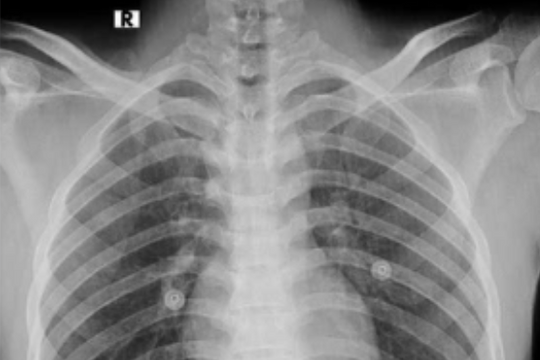

Nam thanh niên 17 tuổi mắc bệnh phổi, suy thận do hút thuốc lá điện tử

Việc hút thuốc lá điện tử của bệnh nhân khi còn thiếu niên đã dẫn tới việc hút thuốc lá điếu và sớm gây ra bệnh phổi tắc nghẽn, suy thận ngay khi còn rất trẻ.